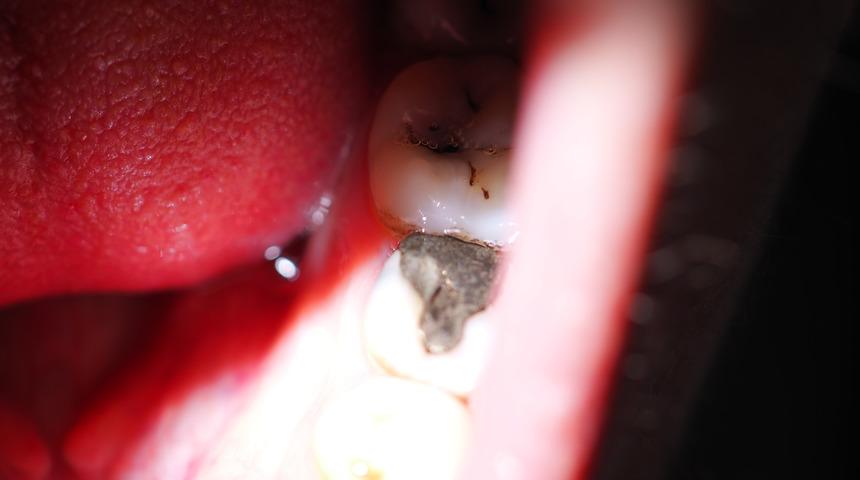

Uykuda yapılan diş sıkmayı bırakmak zor olabilir. Diş gıcırdatma işlemine dikkat edilmezse, mine kaybı ve diş eti çekilmesi gibi uzun vadeli komplikasyonlara yol açabilir. Bu yüzden alışkanlığı teşhis etmek ve frenlemek önemlidir.